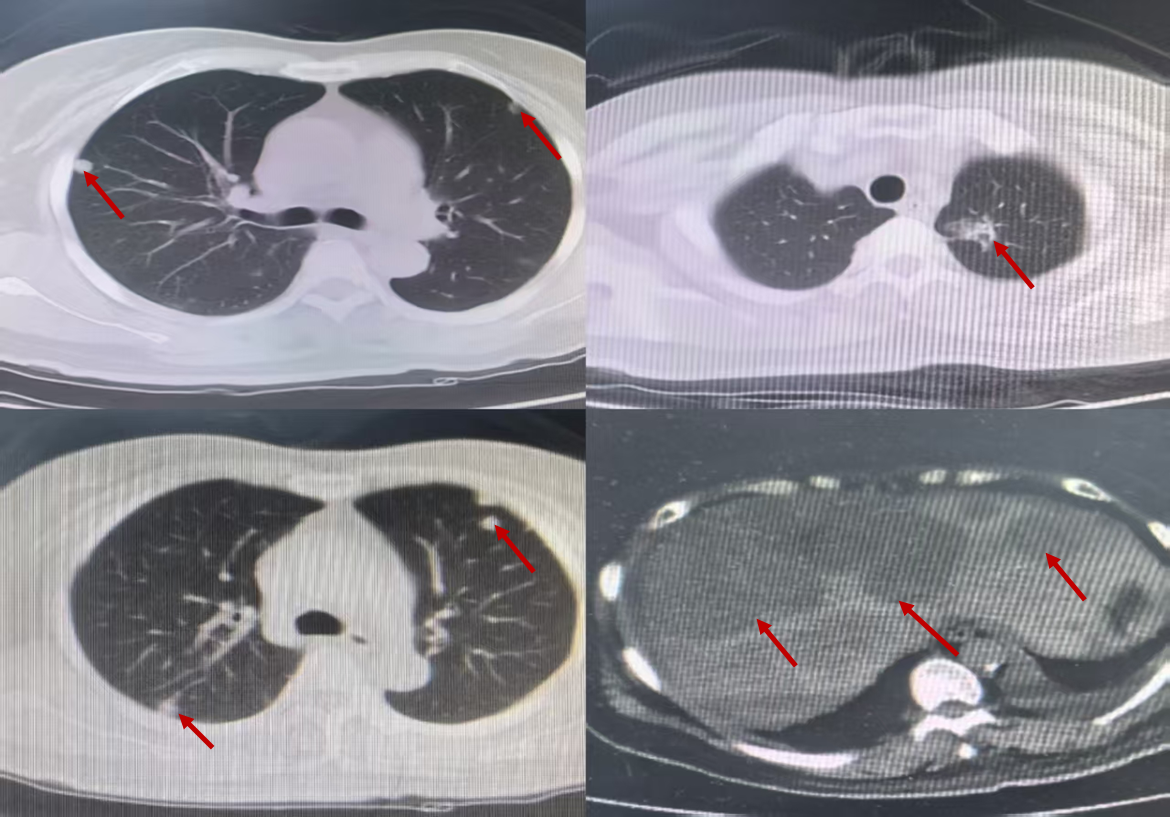

2024年6月21日至今,予“长春瑞滨软胶囊40mg/tiw 连服三周休息一周 Q4W+贝伐珠单抗 400mg d1 Q3W+地舒单抗 120mg ih Q4W”联合治疗,同时针对第四腰椎行放疗以止痛。2025-03-26,复查胸部+上腹部CT(图7):左肺原发灶缩小,双肺新发转移灶稍缩小,肝内多发转移灶较前缩小,边界清楚;颅脑磁共振:未见转移。

目前患者已维持治疗9个月,腰痛症状消失,双肺,肝,骨转移灶均有缩小,无明显胃肠道反应及重度骨髓抑制情况发生。

疗效评估:PR。

截止2025年3月,PFS3:患者已坚持治疗9个月。